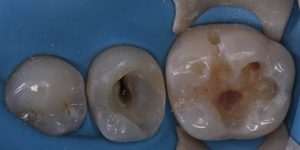

Работы наших специалистов по лечению каналов зуба